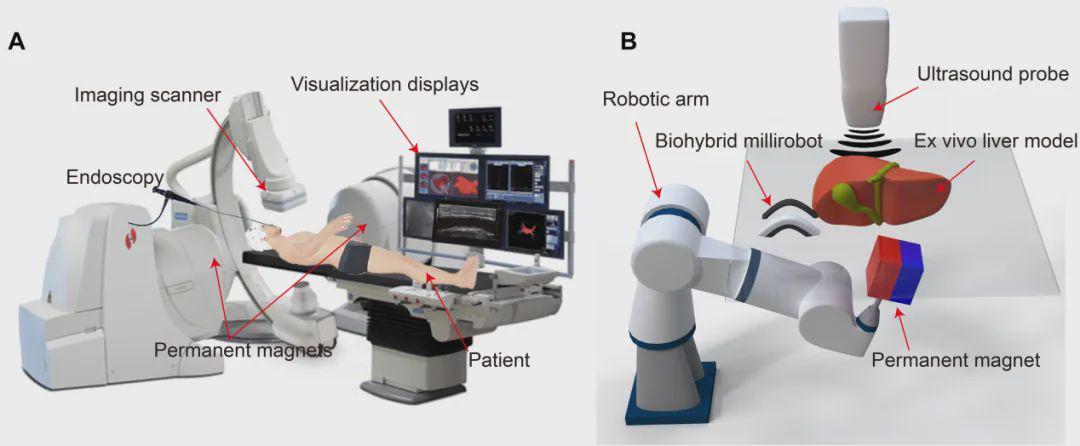

团队开发了一套集成机器人平台,将磁驱系统与超声成像结合,实现了机器人的实时影像引导与闭环控制。

>

>

在离体猪肝模型中的演示令人印象深刻。

2D细胞片机器人(尺寸:6.4×2×0.2 mm)在旋转磁场驱动下,以0.24 mm/s的速度在胆管中实现波动爬行。它能自适应管道尺寸变化,从3mm宽的区域进入仅0.5mm的狭窄段(远超传统内窥镜可达范围),形状从倒C形变为正弦波形。